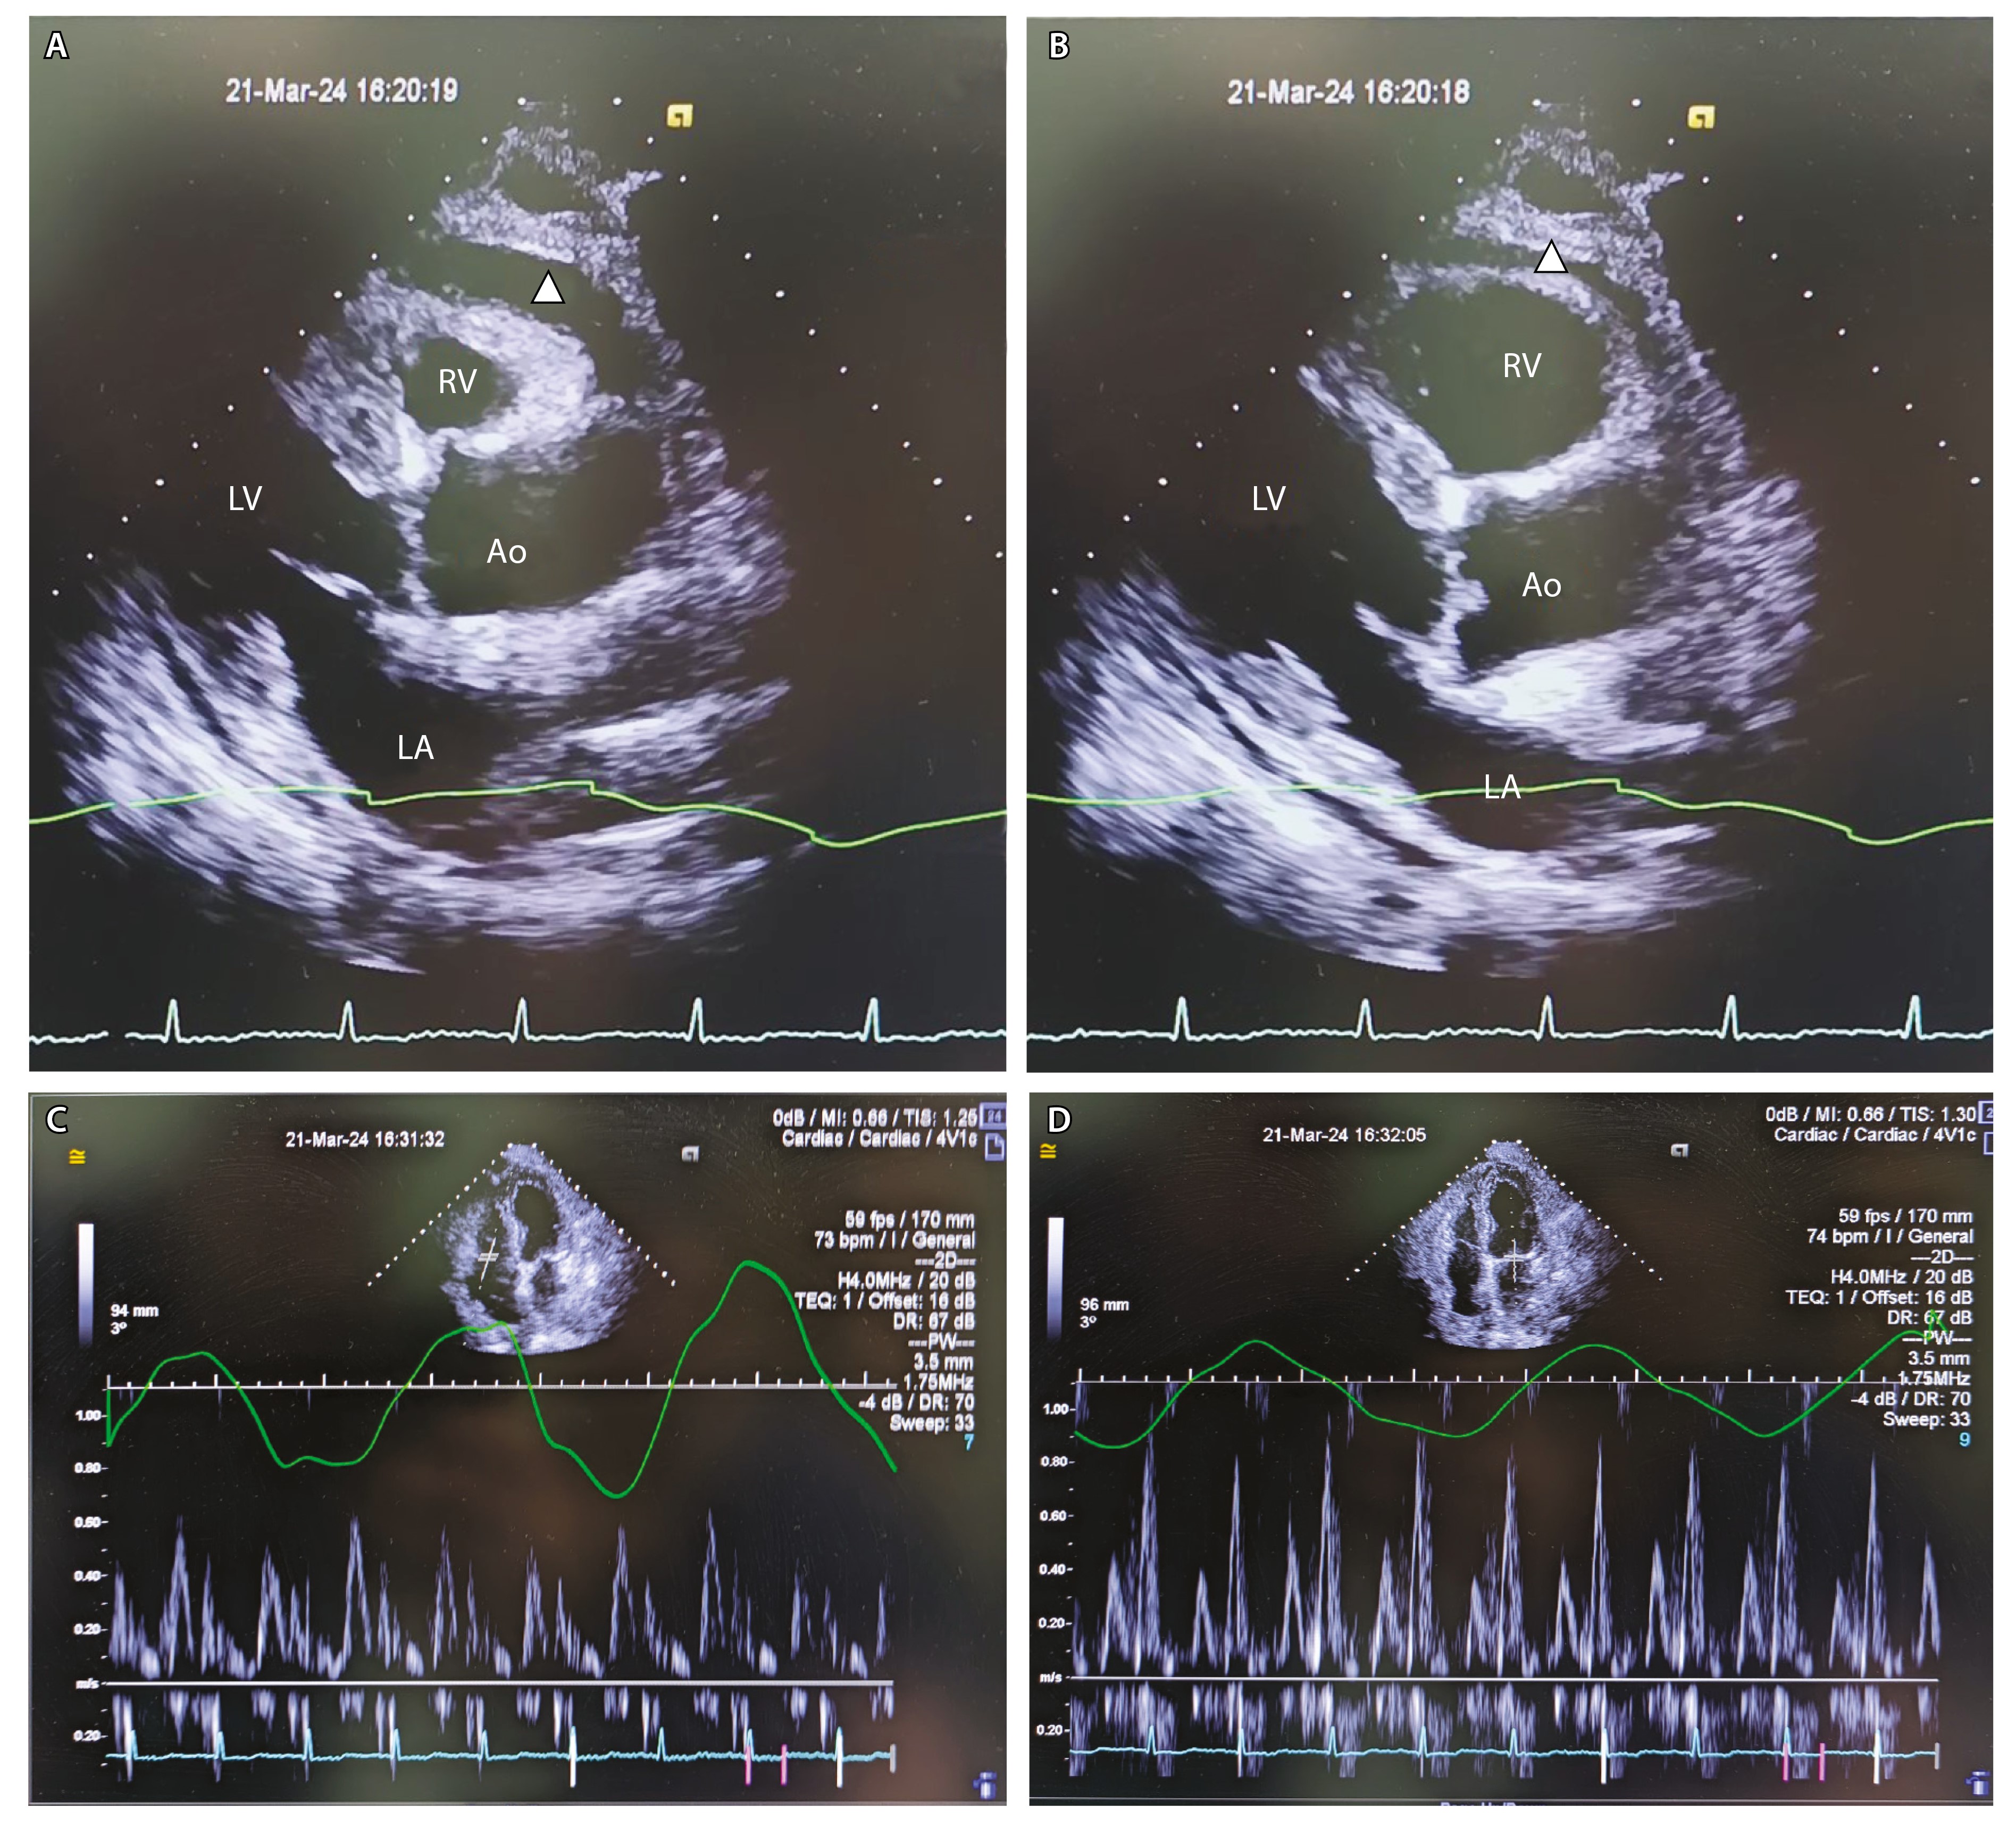

Парааортальное расположение наиболее крупного конгломерата лимфоузлов делало весьма затруднительным получение биопсийного материала для морфологического изучения. В контексте субфебрилитета, изменений в периферической крови, повышения ЛДГ и СРБ внутригрудная лимфаденопатия определяла необходимость онкогематологического обследования. С учетом небольшой протеинурии, дорсопатии и полинейропатии, для исключения парапротеинемических гемобластозов проведено исследование белковых фракций. При уровне общего белка 71 г/л (N – 65–85 г/л) доля альбумина составила 34,72% (N – 54,4–69,7%), альфа-1-глобулина – 9,24% (N – 2,63–5,03%), альфа-2-глобулина – 18,26% (N – 4,87–10,48%), бета-1-глобулина – 3,88% (N – 5,35–9,19%), бета-2-глобулина – 2,39% (N – 2,38–7,11%), гамма-глобулина – 31,52% (N – 9,69–18,9%). В области фракции гамма-глобулинов обнаружен М-градиент, представленный иммуноглобулинами G и каппа (рис. 5).

Рис. 5. Электрофорез белковых фракций. Заштрихован пик в зоне гамма-глобулинов, представленный иммуноглобулинами G и каппа. α-1 – альфа-1-глобулин, α-2 – альфа-2-глобулин, β-1 – бета-1-глобулин, β-2 – бета-2-глобулин, γ – гамма-глобулин